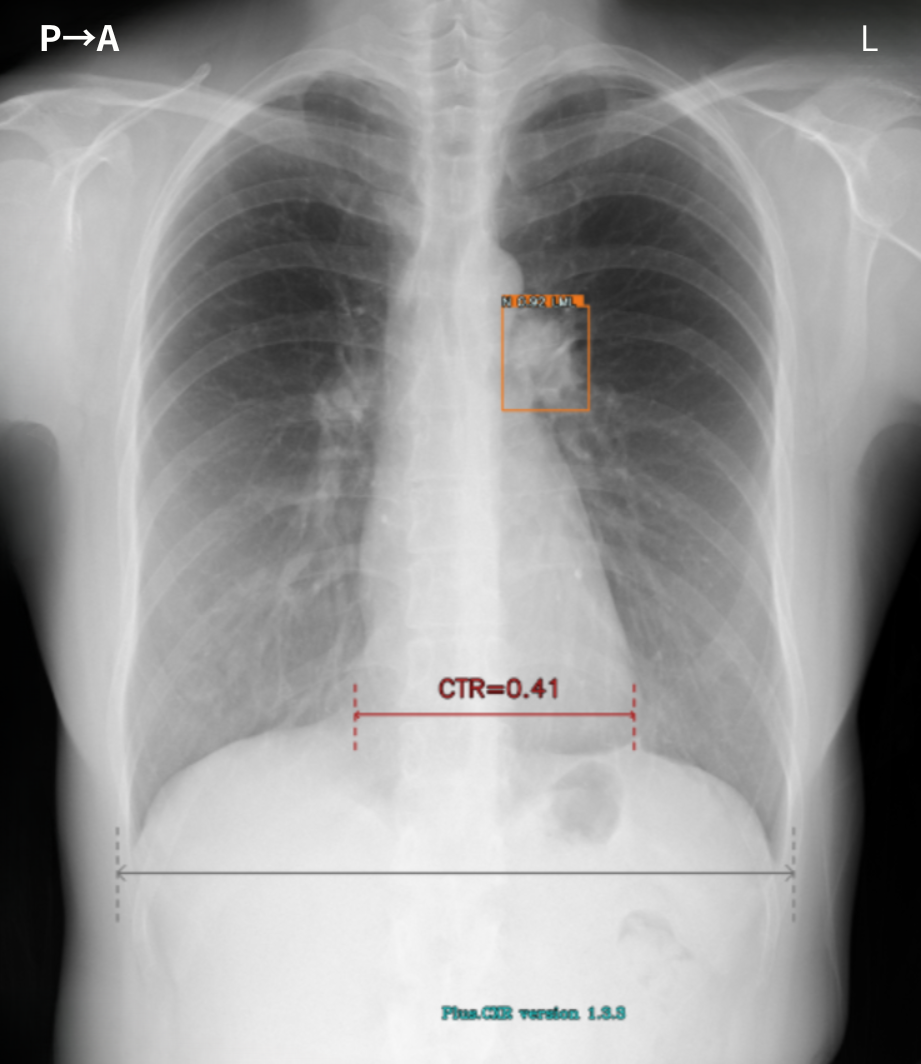

胸部X線AI「Plus.CXR」が指摘する、正常な乳頭陰影や肋骨肋軟骨移行部周囲の軟骨の骨化(Ossification)、各所の胸膜肥厚所見などの精査不要の陰性所見をより短時間でルールアウトできるようになりました。

また、胸部X線AI「Plus.CXR」では著者が通常は指摘できない、径5mm前後の比較的小さな病変を指摘できます。

加えて、肺門部周囲の太い血管陰影とシルエットが明瞭に存在する淡い透過性の低下部を指摘することができました。これらは、十分な集中力で画像を参照していない場合見落とす可能性が高い所見だと思料されます(図1,2,3)。